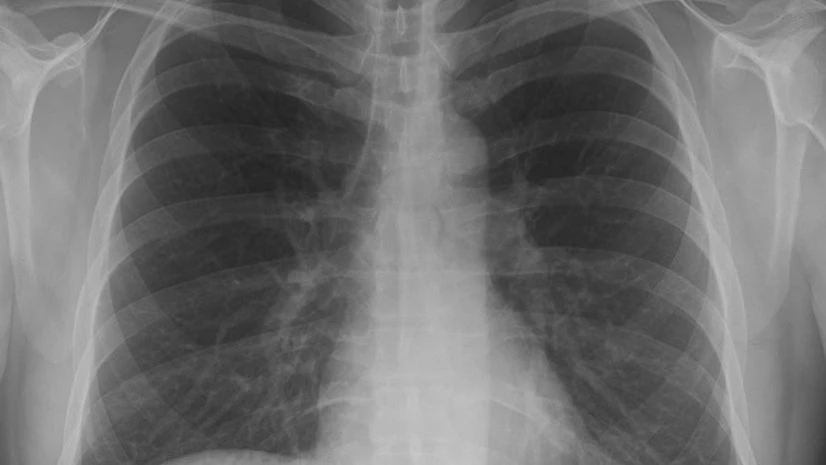

Exposure to even low doses of ionising radiation, such as X-rays, may increase the risk of cardiovascular diseases, a study warns.

It is known that populations exposed to ionising radiation in medical or environmental settings have symptoms suggesting an increased risk of cardiovascular disease.

However, the study suggests that low exposure to doses of around 0.5 gray (Gy) - the equivalent of repeated CT scans - is associated with a significantly increased risk of cardiovascular damage, up to decades after exposure.